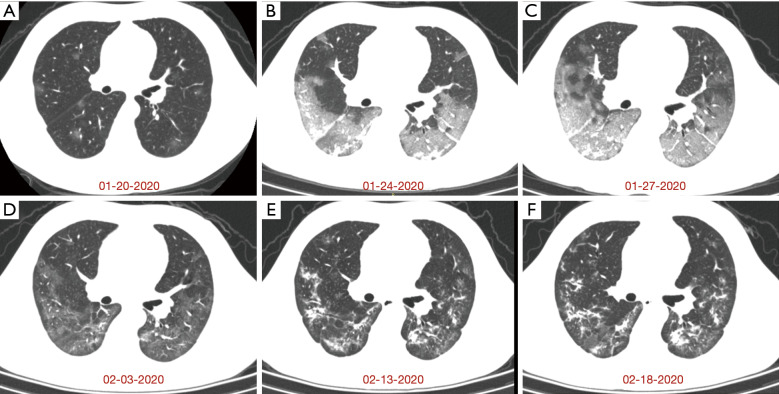

A 40-year-old patient (male) living in Wuhan, was admitted to a fever clinic on January 20, 2020, with symptoms of fever for 2 days. Chest CT revealed multiple ground-glass opacities (GGOs) distributed in the peripheral and peribronchovascular area of bilateral lungs (Figure 1A). The major axis of maximal opacity was 2.8 cm in right lower lobe. Respiratory tract virus antigen and antibody tests, including cytomegalovirus, influenza virus A and B, human parainfluenza virus, respiratory syncytial virus and adenovirus, showed all negative results on January 22, 2020, and SARS-CoV-2 nucleic acid was positive one day later. A 4-day follow-up CT showed multiple GGOs enlarged significantly with multifocal consolidation, interlobular septal thickening, vessel thickening and air bronchogram, which involved all pulmonary segments (Figure 1B). The major axis of maximal lesion was 7.5 cm in right lower lobe. On January 27, 2020, the 2nd follow-up CT illustrated multiple GGOs further enlarged (the major axis of maximal lesion was 10.1 cm in right lower lobe), but consolidation partial absorbed (Figure 1C). After 7 days, the 3rd follow-up CT represented remarkable absorption of multiple GGOs in bilateral lungs and multiple linear consolidation (Figure 1D). The patient remained negative after 2 consecutive RT-PCR tests on February 4 and 6, 2020. The time from symptom onset to recovery was 22 days.

Figure 1.

Series of chest CT images in the recovered and discharged patient with symptoms of fever and shortness of breath again. (A) On January 20, 2020, initial scan for the first hospital admission showed multiple ground-glass opacities (GGOs) in bilateral lungs. (B) A 4-day follow-up scan showed multiple GGOs enlarged with multifocal consolidation, interlobular septal thickening, and vessel thickening. (C) The follow-up CT 3 days later showed GGOs enlarged significantly with interlobular thickening, but some consolidation opacities absorbed. (D) The follow-up CT 7 days later showed the most GGOs absorbed. (E) On February 13, 2020, initial scan for the second hospital admission showed progression from some GGOs to multifocal consolidation. (F) A 5-day follow-up scan showed consolidation opacity enlarged in left lower lobe.

After hospital discharge, the patient was isolated at home for 5 days. On day 27 of illness, the patient had a fever again (38.2 °C), and CT showed some GGOs absorbed but others progressed to multifocal organizing consolidation in bilateral lungs (Figure 1E). Positive RT-PCR test results and laboratory studies suggested inflammatory situation, with lymphocyte count 0.70 (normal: 1.10–3.20)×109/L, erythrocyte sedimentation rate 68 (normal: 0–15) mm/H, procalcitonin 0.15 (normal: 0.02–0.05) ng/mL, and lactate dehydrogenase (LDH) 293 (normal: 135–225) U/L.

On February 18, 2020, the follow-up CT showed some consolidation enlarged in left lower lobe and right upper lobe, while other linear consolidation remained (Figure 1F). Moreover, laboratory studies matched the progressive CT findings, with ferritin 1,846.5 (normal: 30–400) µg/L, procalcitonin 0.13 (normal: 0.02–0.05) ng/mL, interleukin-2 receptor 1,108 (normal: 223–710) U/mL, interleukin-6 9.97 (normal: <7) pg/mL, interleukin-10 10.2 (normal: <9.1) pg/mL, and tumor necrosis factor 15.7 (normal: <8.1) pg/mL. From February 13, 2020, the patient was admitted to the isolation ward and received antibiotic, antiviral, hormone, and stomach-protecting therapies once again.